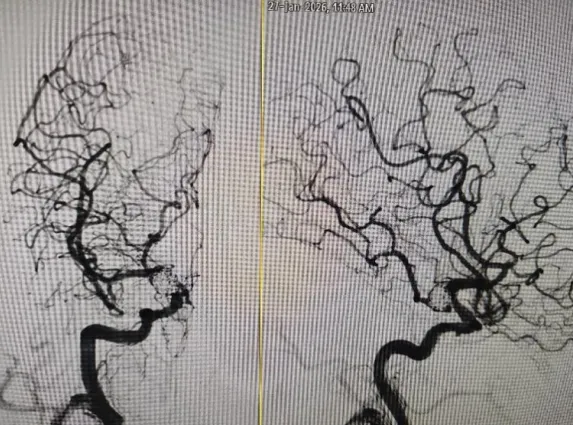

时间回溯到2025年12月的一个清晨,甘奶奶(化名)突发剧烈头痛,被紧急送往当地医院就诊。经CT检查被确诊为蛛网膜下腔出血,进一步CTA检查发现,患者颅内双侧颈内动脉后交通段有动脉瘤,且已发生破裂出血,病情危重。考虑到患者年事已高、手术风险大,当地医院受限于诊疗条件,采取保守治疗。虽暂时缓解了头痛症状,但动脉瘤这一核心隐患始终未除,家属的担忧丝毫未减。抱着最后一线希望,家属带着甘奶奶来到我院神经外科寻求进一步救治。

▲CTA双侧颈内动脉后交通段动脉瘤